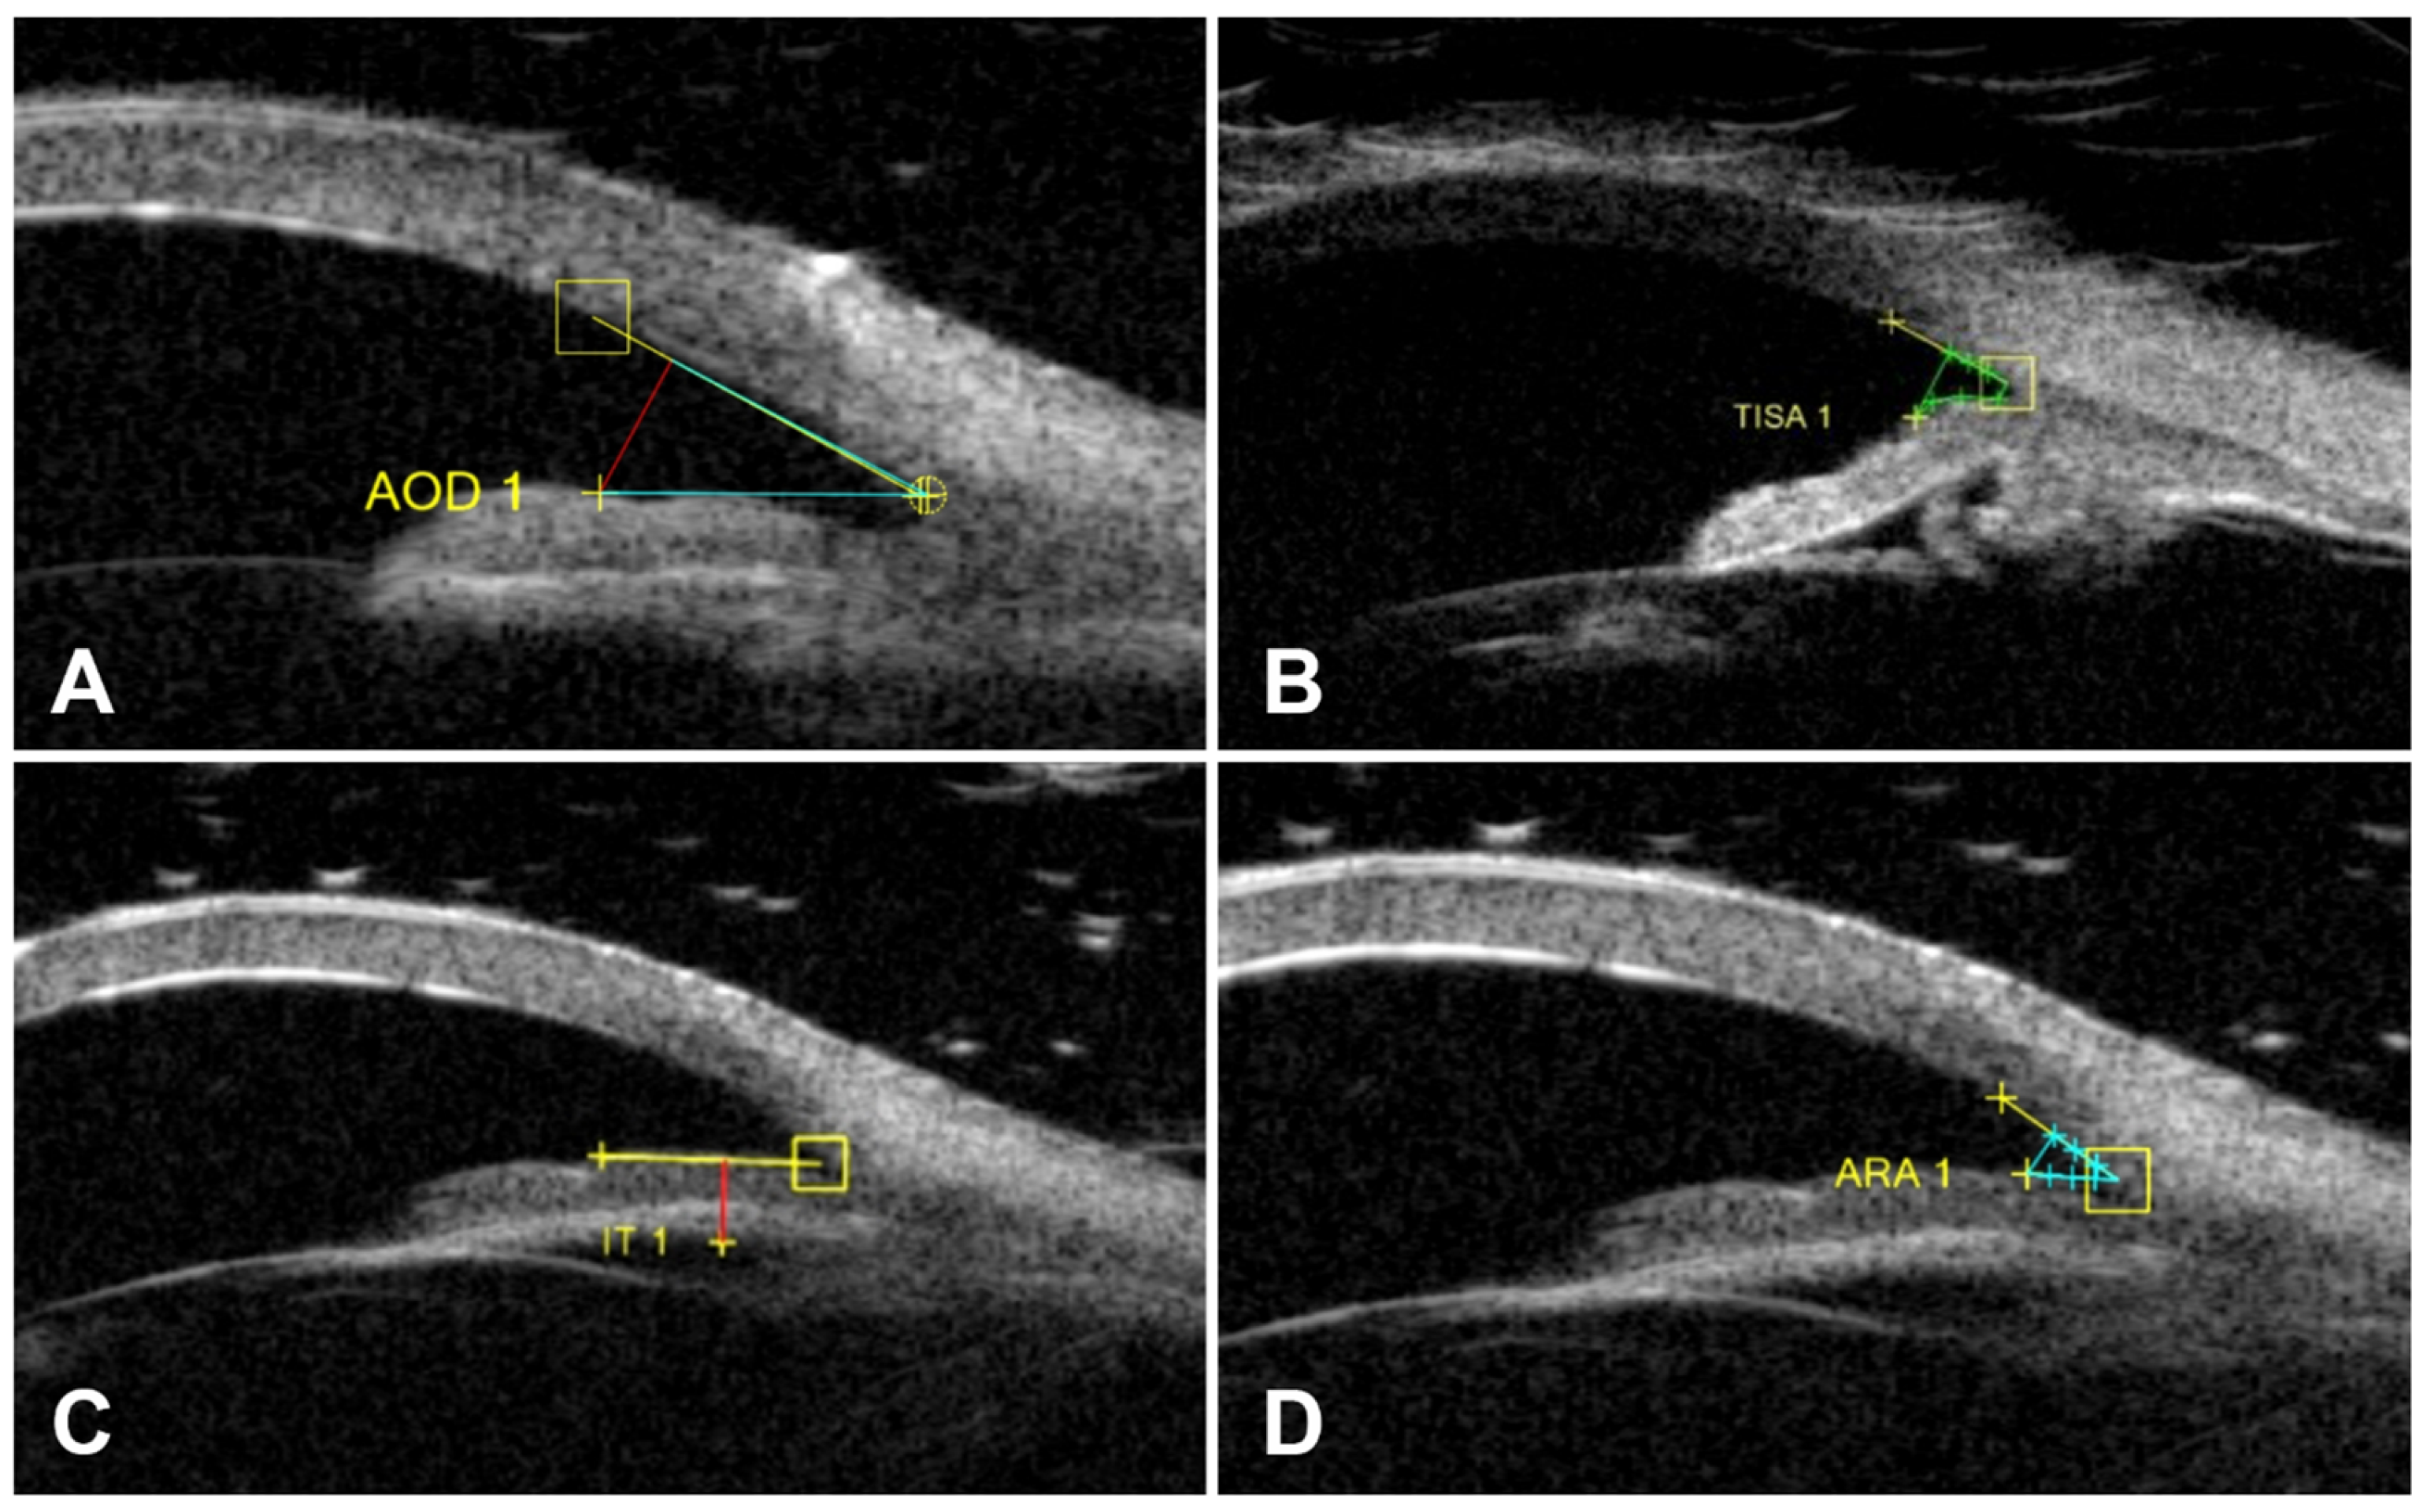

| AOD500 (mm) | 0.99 ± 0.37 | 0.97 ± 0.39 | 0.250 | 0.009 |

| TIA500 (°) | 42.57 ± 7.73 | 41.28 ± 8.08 | 0.021 * | 0.036 |

| IT750 (mm) | 0.55 ± 0.08 | 0.57 ± 0.10 | 0.405 | 0.005 |

| ARA500 (mm2) | 0.15 ± 0.06 | 0.15 ± 0.08 | 0.389 | 0.005 |

| TISA500 (mm2) | 0.16 ± 0.07 | 0.15 ± 0.08 | 0.190 | 0.012 |